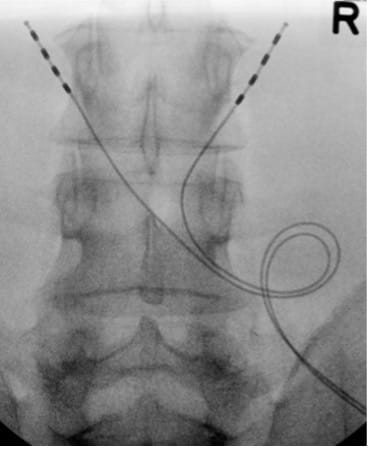

- Obtain PA view centered at L3, visualizing L2 and L4.

- Place marker 22G or 25G spinal needles bilaterally at L3 TP–SAP junction; confirm tip at superior TP border on the lateral view.

- Repeat on the contralateral side.

- Create an IPG pocket; tunnel leads from the inferolateral tension-relief loop pocket to the IPG pocket; test impedances and motor responses again with the IPG in the IPG pocket.

- Form tension-relief loops without sharp bends or significant friction points; tuck the loop into the tension-relief loop pocket.